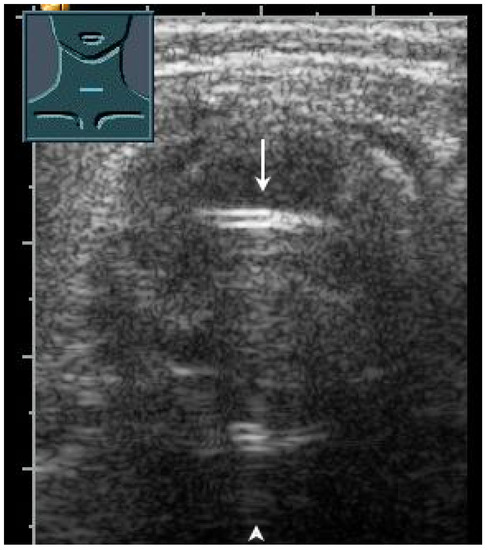

Figure 28.

Demonstration of correct tracheal intubation. Only one air–mucosa interface within the lumen of the trachea (arrow) with comet-tail artifacts (arrowhead) and dorsal sound extinction is visualized.